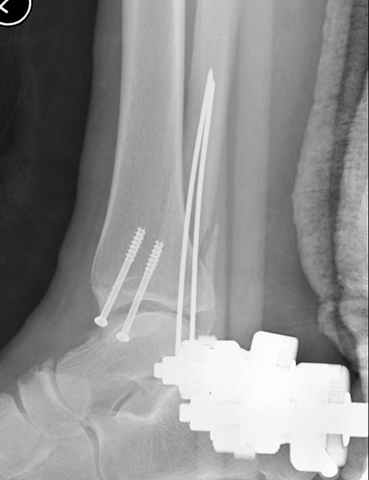

A propos fibular fixation if one is eager to stabilize it separately. In the fracture pattern a way of closed fixation by V-shaped stressed wire (advanced by colleagues from Moscow, prof. Lazarev A.F. et al.) must be excellent. We use indirect closed reduction by the external fixator. Example attached, that fibular fracture is even more suitable for plating but the wire did the job.

I didn't perform stress tests, at least it prevents fibula against secondary displacement. Stressed 2 mm double wire is not so weak.

I used it only in two fibular cases recently. Colleagues from Moscow use the wires mostly for proximal humerus and even femoral neck.

АЧ>> фиксации напряженной V-образной спицей.

Идея хорошая, особенно если короткий и поперечный перелом. Узнал о методе на прошлогодней конференции в Санкт Петербурге, доклад от ЦИТО,

и в доказательство Александр показал на своих снимках оригинальность метода, концепция "сделай сам имплант" из малого разреза и доступность. (при совершенствовании методики и инструментарии, метод может быть применен и в других случаях)